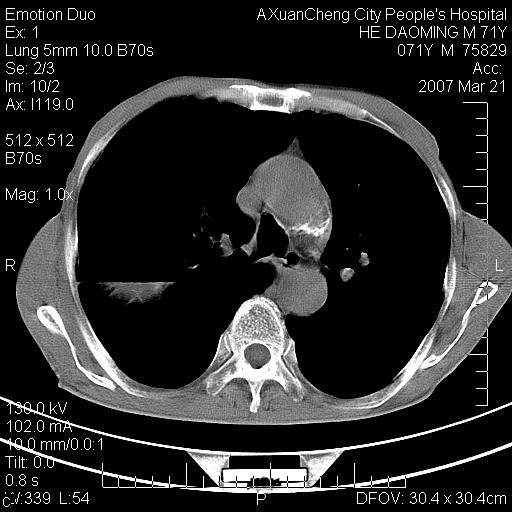

标题: CT7269:[原创] 咳嗽,咳痰,大家讨论右肺病变的部位 [打印本页]

标题: CT7269:[原创] 咳嗽,咳痰,大家讨论右肺病变的部位

1.慢支肺气肿 肺心病 肺大泡;2.叶间裂积液,前胸膜粘连

右侧相当于叶间软组织样密度ct值约50hu,请大家讨论是什么性者病变

右下肺大囊肿伴感染.肺气肿,肺大泡.

考虑:慢性支气管炎合并全小型肺气肿、肺大泡、间质纤维化、感染,右斜裂积液。

考虑慢支,肺气肿,肺大泡,间质纤维化;右侧斜裂液气胸考虑(可能因为肺大泡破裂破入斜裂所致).

考虑病变以右上中肺多发肺大泡为主并感染。请结合临床考虑慢支肺气肿,肺心病。